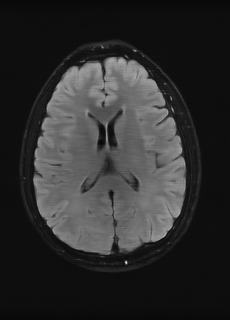

As we observe from the right image in Fig. 2, our BRM, both from MIMO and SISO settings, predicts the performance of dedicated models with a high correlation. We further choose the best three , and perform the last stage of fine-tuning accordingly to (6). A visual evaluation on real data is shown in Fig. 3. For simulated data, please refer to the Supplemental Material section.

Base on the best performing , we perceive that among , , and FLAIR, the results are best when is sampled the most. We suggest that this makes intuitive sense as images provide the best contrast out of the three sequences, which can compensate for the details lost in other images. The same observation can be made on the simulated data, where both and FLAIR show good contrast. When the time setting is changed to non-uniformity, we can see that our search for the best sampling strategy reflects the change. is sampled more as a result of faster acquisition time, while is still sufficiently sampled.

| Sequence | LR | SISO | MIMO | MIMO tuned | GT |

|---|---|---|---|---|---|

(a) 34.38/0.9371

(a) 34.38/0.9371

|

(b) 42.42/0.9883

(b) 42.42/0.9883

|

(c) 44.60/0.9920

(c) 44.60/0.9920

|

(d) 45.50/0.9940

(d) 45.50/0.9940

|

(e) PSNR/SSIM

(e) PSNR/SSIM

|

|

(f) 29.74/0.8903

(f) 29.74/0.8903

|

(g) 36.25/0.9734

(g) 36.25/0.9734

|

(h) 36.42/0.9752

(h) 36.42/0.9752

|

(i) 37.70/0.9832

(i) 37.70/0.9832

|

(j) PSNR/SSIM

(j) PSNR/SSIM

|

|

(k) 39.89/0.9311

(k) 39.89/0.9311

|

(l) 43.94/0.9864

(l) 43.94/0.9864

|

(m) 44.74/0.9883

(m) 44.74/0.9883

|

(n) 45.49/0.9894

(n) 45.49/0.9894

|

(o) PSNR/SSIM

(o) PSNR/SSIM

|